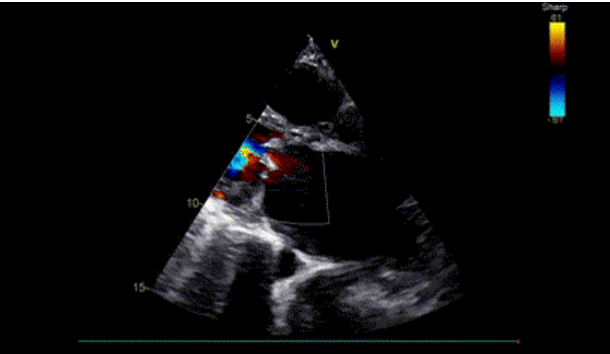

TEE: Type IB left atrial appendage thrombus, thin interatrial septum, no significant mitral regurgitation.